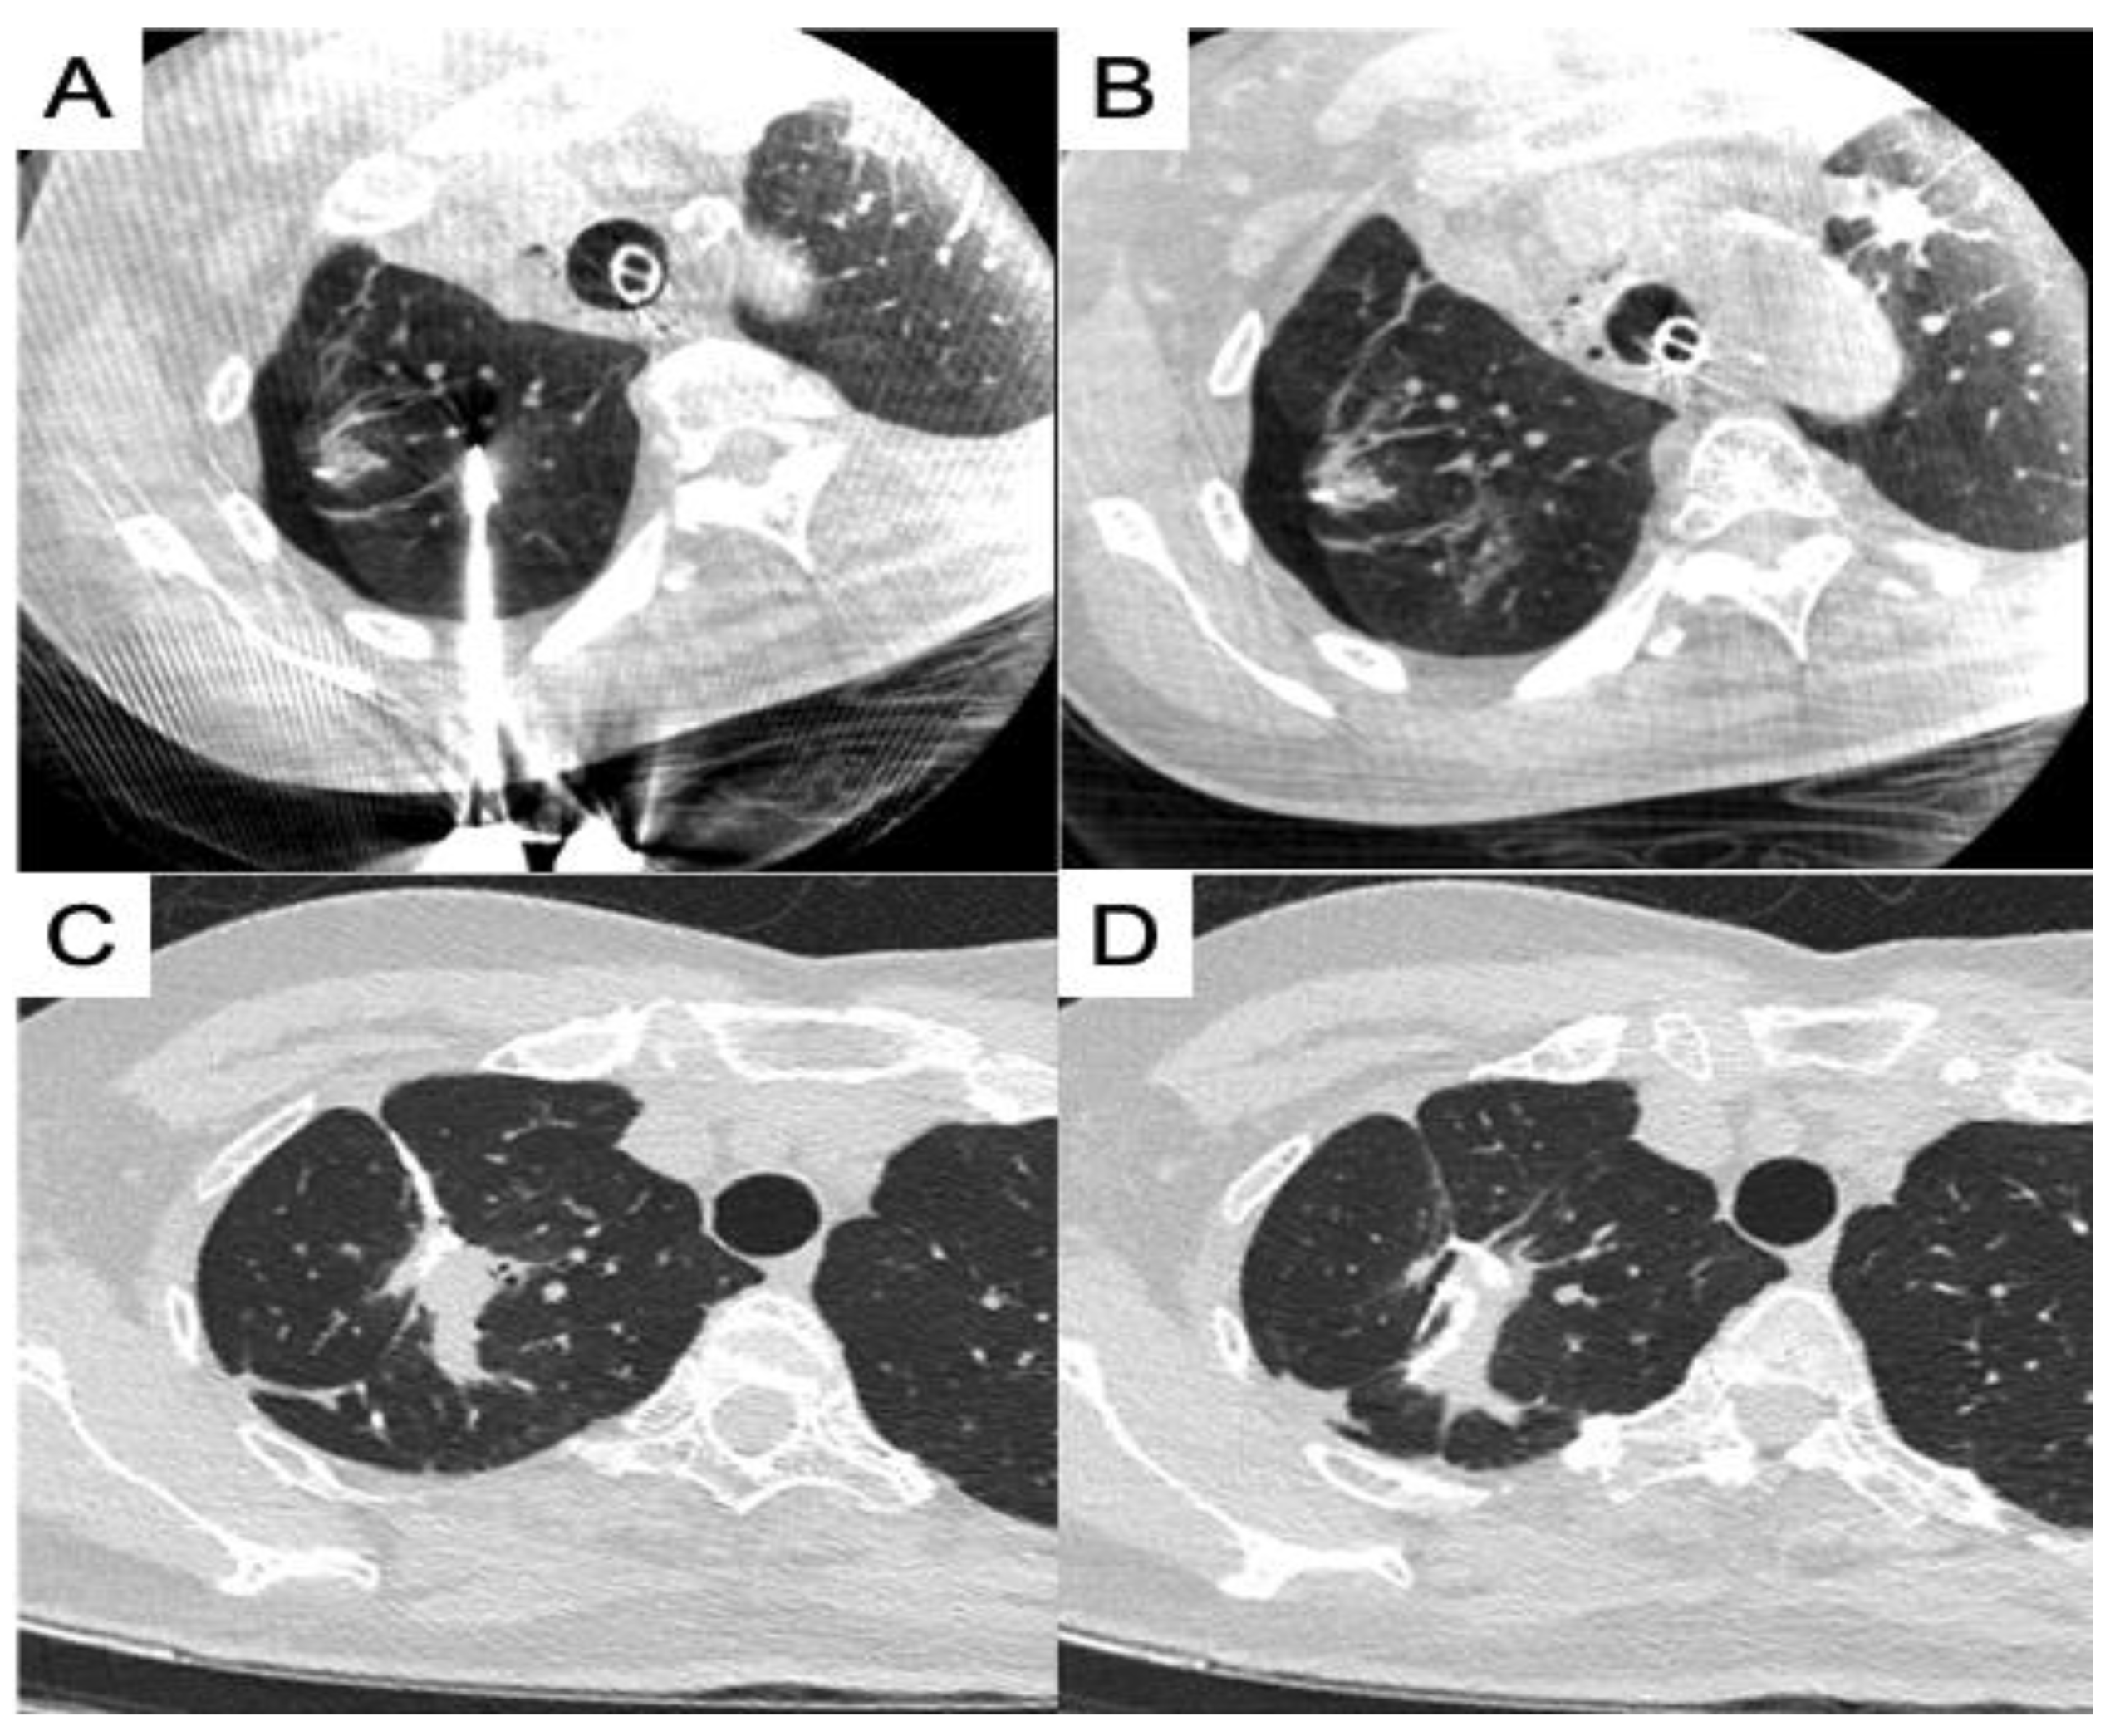

- Chang, L.K.; Yang, S.M.; Chung, W.Y.; Chen, L.C.; Chang, H.C.; Ho, M.C.; Chang, YC.; Yu, C.J. Cone-beam computed tomography image-guided percutaneous microwave ablation for lung nodules in a hybrid operating room: an initial experience. Eur Radiol 2024, 34, 3309–3319. [Google Scholar] [CrossRef] [PubMed]

- Chan, P.S.; Chang, L.K.; Malwade, S.; Chung, W.Y.; Yang, S.M. Cone beam CT derived laser-guided percutaneous lung ablation: minimizing needle-related complications under general anesthesia with lung separation. Acad Radiol 2024, S1076-6332(24)00284-8. [Google Scholar] [CrossRef]